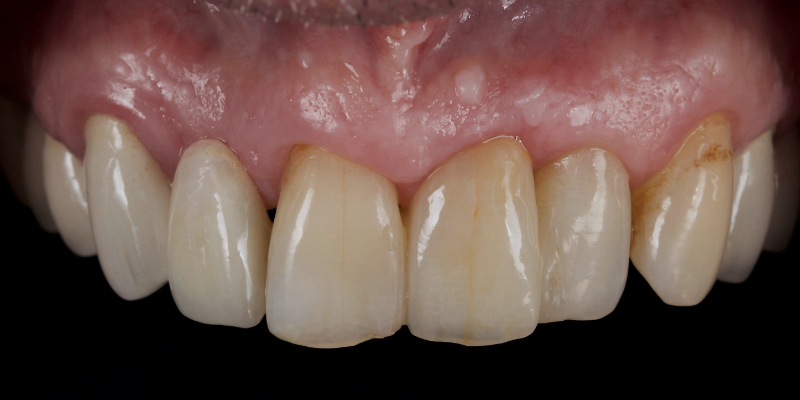

An e.max (lithium disilicate), one-wing (adjacent central being the retainer) bridge was placed, which resulted in an acceptable outcome (Figs. 2-4) that was more timely and at a lower financial and biological cost to the patient than the implant Arthur initially thought he wanted.